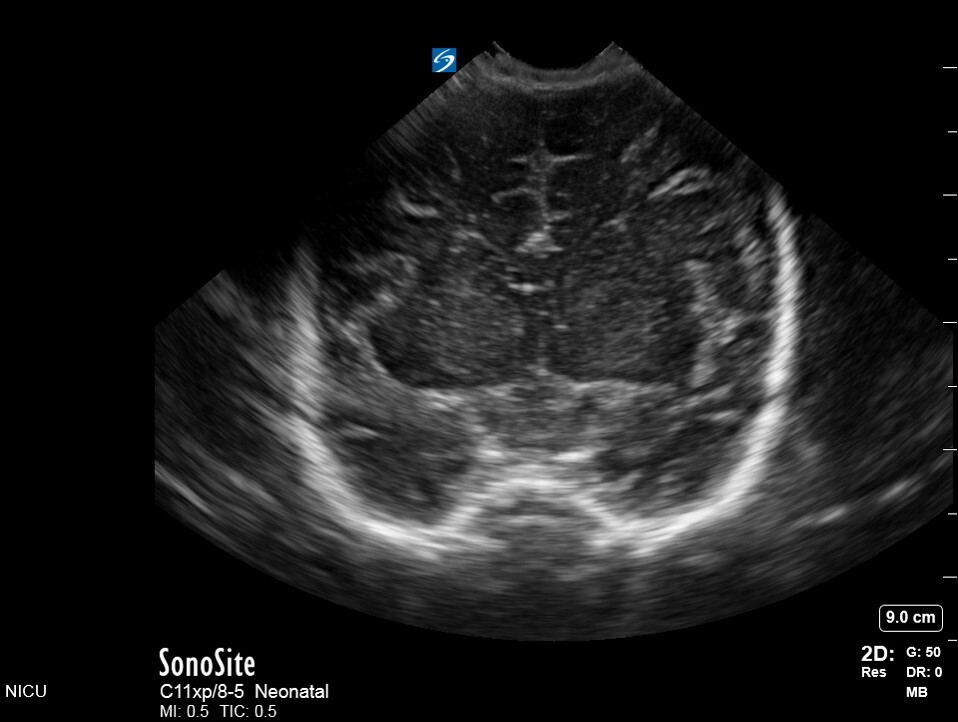

Neonatology C2 1 Image